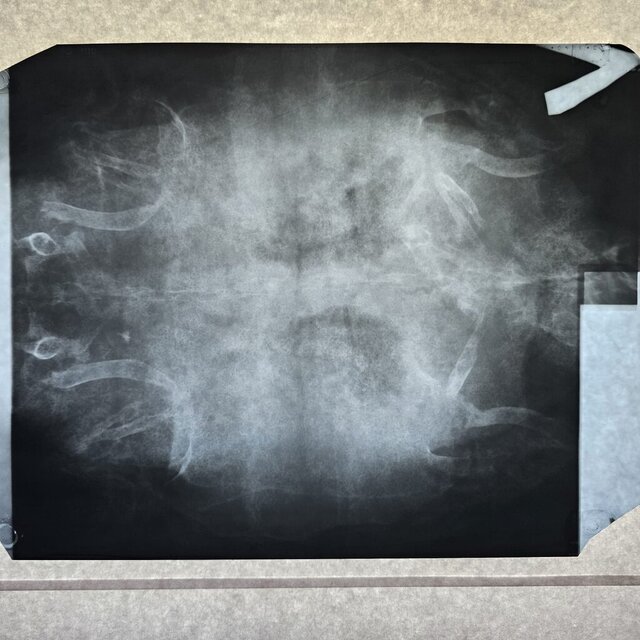

Добрый день. Сходили в клинику Степаненко в Харькове, но приём вела не она. Сдали кровь её удалось взять очень мало. Сделали ренген. Получили назначения. Там нам вкололи Элеовит. Сказали что все очень плохо. Анализ крови скину завтра клиника не прислала

Назначения из клиники